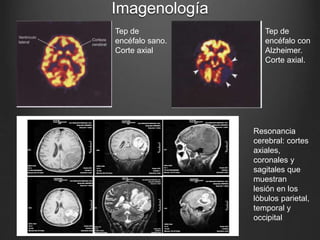

Tep de

encéfalo sano.

Corte axial

encéfalo con

Alzheimer.

Corte axial.

Resonancia

cerebral: cortes

axiales,

coronales y

sagitales que

muestran

lesión en los

lòbulos parietal,

temporal y

occipital

• #16 En las de arriba lo amarillo son las áreas de la corteza con metabolismo activo, en la con alzhimer se ve el defecto del metabolismo en la corteza en donde apuntan las flechas. La de abajo es la resonancia cerebral en tres cortes diferentes que muestran la misma lesiòn, que afecta los lóbulos parietales temporales y occipitales.